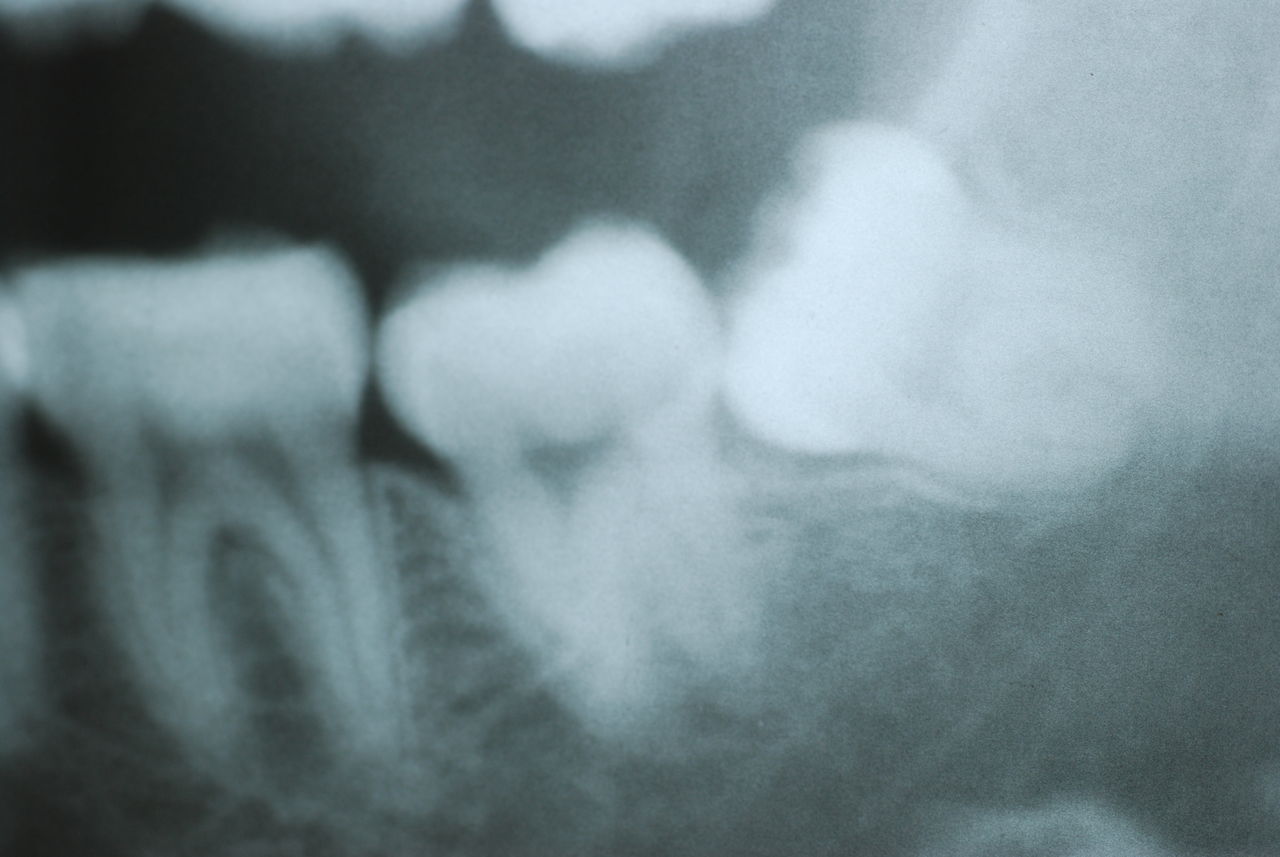

上の歯は一本がブラブラでしたね。

下顎が右にシフトしているので噛み合わせはとても慎重にしました。下の方が頬側にないと安定せず噛めないのです。